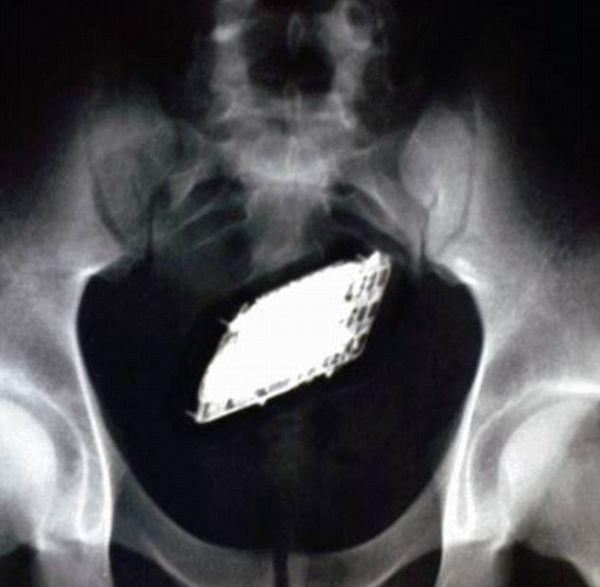

ブラジルの囚人たちが刑務所内に携帯電話を密輸する方法

もちろん刑務所内に携帯電話を持ち込む事はどの国であろうと厳密に禁止されているが、ブラジルの囚人たちの創造力は意外にも豊かだったりする。ただ残念な事にこれらはすべて失敗した例であるが。[7]images